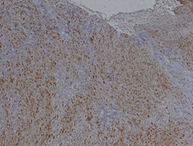

The histological examination reveals a spindle-shaped tumor

proliferation arranged in bundles. It consists of spindle cells without visible

cytoplasmic boundaries, arranged in short or intertwined bundles, with nuclear

palisades and cellular whorls. The cells have elongated nuclei, which are

non-atypical. The blood vessels have thin walls. Immunohistochemical analysis

demonstrates diffuse expression of pS100 in tumor cells. They did not express

CD34, EMA, or AML. (Figure 4)

Definitive diagnostic of schwannoma was favored. After a one-year follow-up,

Figure 4: Histological aspect